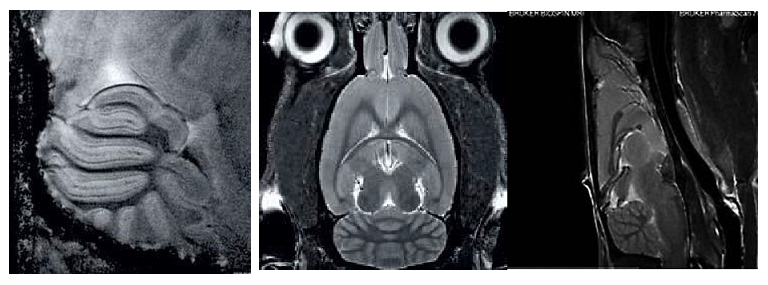

1、高分辨率神經(jīng)解剖結(jié)構(gòu)

布魯克結(jié)合超高磁場,先進(jìn)的相陣控線圈和譜儀技術(shù)提供完美品質(zhì)的結(jié)構(gòu)形態(tài)成像。超高空間分辨率可以顯示精細(xì)的顯微組織結(jié)構(gòu)。領(lǐng)先的磁共振成像技術(shù)在超高磁場下提供完美的對比度。

磁共振成像低溫探頭增加150%的靈敏度,清晰顯示小鼠腦部細(xì)胞層狀結(jié)構(gòu)(小腦的顆粒層和浦肯雅細(xì)胞層),空間分辨率達(dá)到 50μm: